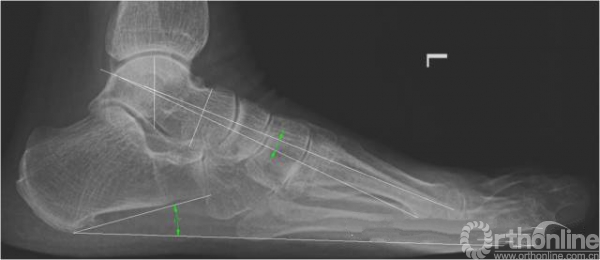

3. X线检查结果

X线检查